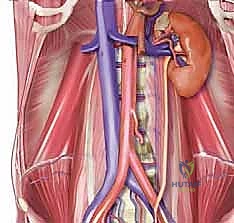

الخطوة الثانية: التعامل مع الأوعية الدموية بمهارة فائقة

هذه هي المرحلة الأكثر دقة. يجب على الجراح إزاحة الأوعية الدموية الرئيسية (الشريان الأبهر والوريد الأجوف) برفق شديد لكشف الجزء الأمامي من العمود الفقري. غالباً ما يستعين الدكتور هطيف بخبراته الواسعة في التشريح الدقيق لضمان عدم حدوث أي مضاعفات.

- تخطيط الأوعية الدموية: نظراً لأن الجراحة تتم من الأمام (بالقرب من الشريان الأبهر والوريد الأجوف السفلي)، يتم في بعض الأحيان إجراء تخطيط للأوعية الدموية لضمان مسار جراحي آمن تماماً.